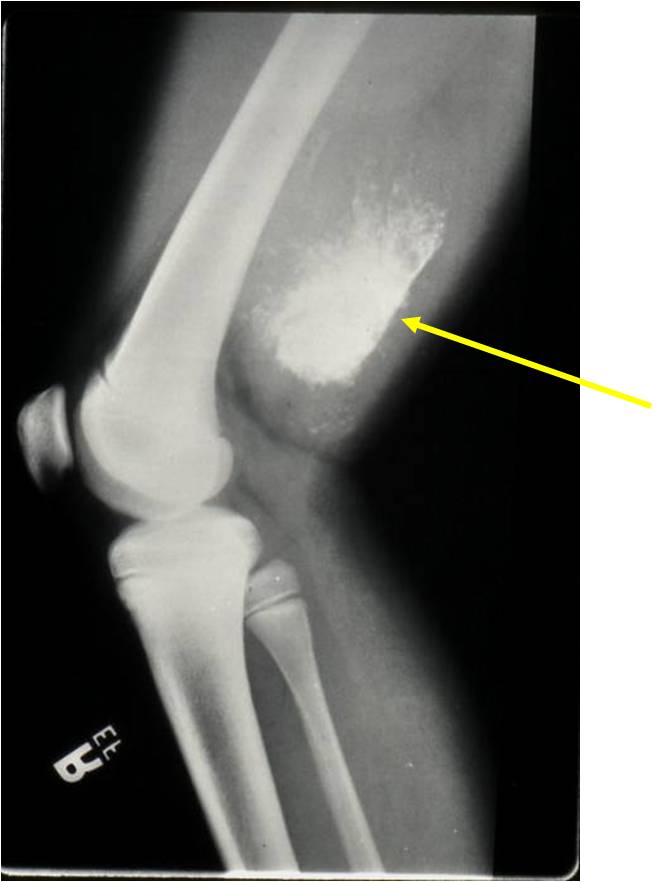

- Aggressive motheaten to permeative lesion

- Indistinct border in most cases

- Osseous destruction with a soft tissue component

- Chondroid matrix calcification may be present (60-70% of cases)

- Soft tissue mass